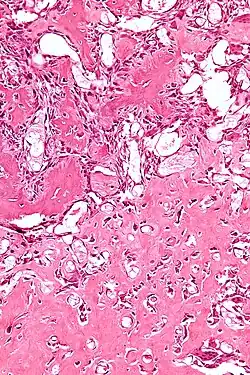

A etiologia do osteoblastoma é desconhecida. Histologicamente, os osteoblastomas são similares aos osteomas osteóides. Embora o tumor seja geralmente considerado benigno, uma variante agressiva tem sido descrita na literatura, com achados histológicos semelhantes a tumores malignos como o osteossarcoma.